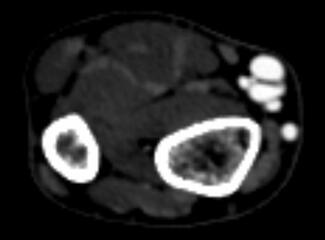

The authors present a case where a migratory bullet was extracted safely using a snare and a Protrieve sheath, a novel device designed to trap thromboemboli in the inferior vena cava during mechanical thrombectomy procedures.